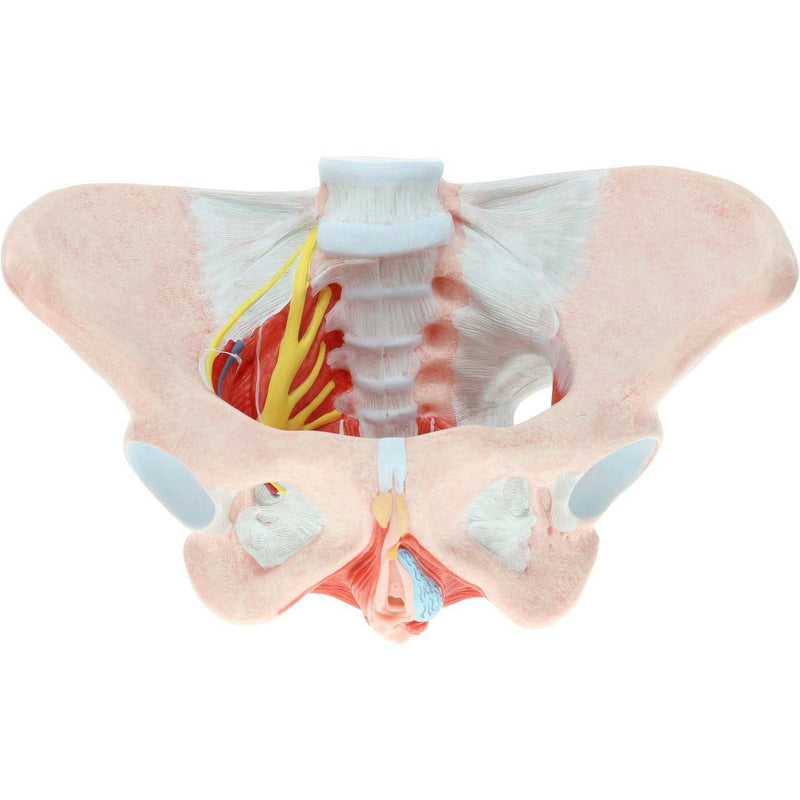

女性骨盤モデル(靭帯、血管、神経、骨盤底筋付き)

この実物大の女性骨盤は、仙腸靭帯、骨盤底筋、神経網および仙骨血管とともに、骨盤の外性器および内性器の構造を手描きで示しています。筋肉や靭帯の筋理を細かく描写しており、このモデルに高品質で詳細な印象を与えています。このモデルは女性の骨格系を理解するための優れた学習教材であり、すべての学生に適しています。さらに、神経痛、筋肉の緊張、靭帯の損傷を患者に説明する際にも役立ちます。拡張現実を用いたインタラクティブな三次元解剖モデルと併用することで、学習を促進し支援する優れたツールとなります。このプラットフォームは、学生が個々の器官の構造を比較・対照しながら解剖モデルの比較分析に取り組むことを可能にします。また、この取り組みは継続教育の場を提供し、すべての学生が解剖学、生理学および病理生理学の知識を深める機会を提供します。

女性骨盤モデル(靭帯、血管、神経、骨盤底筋付き)

この実物大の女性骨盤は、仙腸靭帯、骨盤底筋、神経網および仙骨血管とともに、骨盤の外性器および内性器の構造を手描きで示しています。筋肉や靭帯の筋理を細かく描写しており、このモデルに高品質で詳細な印象を与えています。このモデルは女性の骨格系を理解するための優れた学習教材であり、すべての学生に適しています。さらに、神経痛、筋肉の緊張、靭帯の損傷を患者に説明する際にも役立ちます。拡張現実を用いたインタラクティブな三次元解剖モデルと併用することで、学習を促進し支援する優れたツールとなります。このプラットフォームは、学生が個々の器官の構造を比較・対照しながら解剖モデルの比較分析に取り組むことを可能にします。また、この取り組みは継続教育の場を提供し、すべての学生が解剖学、生理学および病理生理学の知識を深める機会を提供します。